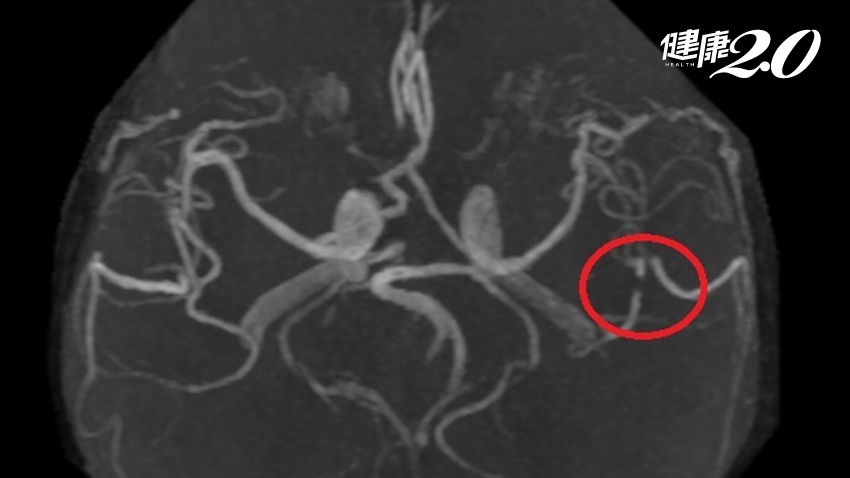

▲ 從電腦斷層中發現,許阿嬤左腦有梗塞現象。

陳惠萱表示,透過腦部核磁共振發現阿嬤的左腦頂葉區域出現梗塞,導致腦功能喪失,也會引起臨床上特殊的表現,稱為「格斯特曼症候群」(Gerstmann syndrome,GSS),其他可能還包括使用物品方面功能的喪失,有的語言理解表達也會受到影響。阿嬤經2周藥物及復健治療,症狀已改善許多。